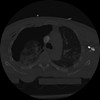

22 ANGIO,CE,Vol,0.5,ANGIO,,